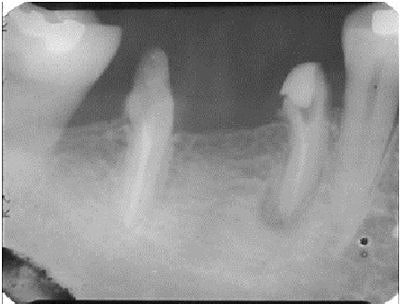

This patient had a periapical lesion around his lower left second bicuspid and the mesial root of his first molar (Nos. 19 and 20). The mesial root of the molar was decayed, but the distal root was in good condition. I decided to perform root canal therapy, hemisect the molar and remove the mesial root, obturate the canals with Pulpdent Root Canal Sealer, and see if I could stimulate healing of the periapical lesion. If the treatment failed, extraction could be performed at a later date.

I had seen periapical healing after obturating canals with Pulpdent Root Canal Sealer and was willing to give it a try. The small extrusion of sealer past the apex is not a concern, but, in any event, the material is biocompatible and usually resorbs over time.

In this case, healing occurred, and a radiograph taken five months later shows resorption of the extruded sealer and healing of the periapical lesion.